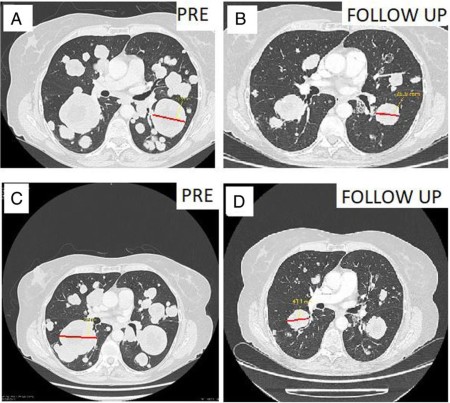

Report of the Month: Persistent response to vemurafenib in metastatic ameloblastoma with BRAF mutation

Ameloblastomas are uncommon locally aggressive tumors of odontogenic epithelium that rarely metastasize. Here, we report a case of a 33-year-old woman with ameloblastoma diagnosed 30 years ago who developed asymptomatic lung metastasis 19 years ago. Although cases of disseminated stage IV ameloblastoma are exceedingly rare, our observations suggest the possibility of introducing neoadjuvant or targeted therapy to improve outcomes and minimize functional and cosmetic morbidity. (Broudic-Guibert et al., 2019)